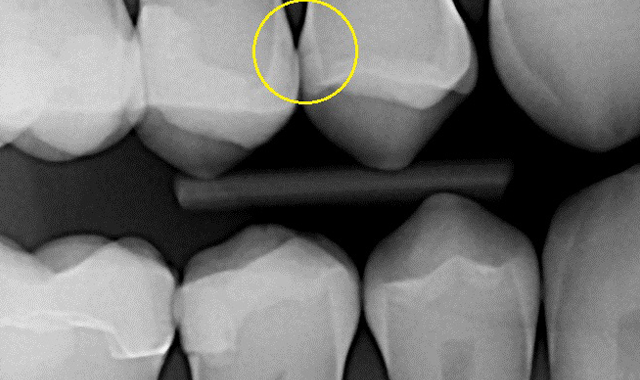

Fig. 1 Radiograph

During a six month recall exam, radiographs were updated for a 46 year old male with a history of routine preventive care and excellent oral hygiene (Fig. 1). Early carious lesions were evident on the mesial surface of tooth #4 (maxillary right second bicuspid) and distal surface of tooth #5 (maxillary right first bicuspid) but appeared to be confined to the outer half of the enamel, and did not involve the dentin. Typically, the dental hygiene assessment concludes with a caries risk assessment and discussion related risk factors with the patient. The final assessment, diagnosis and treatment plan are left for the doctor to determine if the decay has extended beyond the dentin-enamel junction (DEJ), and also to determine if the tooth requires treatment, monitoring or remineralization; sometimes a difficult decision.